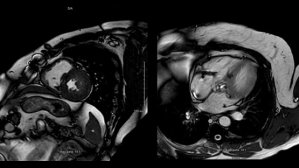

Ce patient de 86 ans est hospitalisé pour des lésions dermatologiques aspécifiques. Il présente plusieurs facteurs de risque cardiovasculaire : un tabagisme ancien, un diabète de type 2, de l’hypertension, une dyslipidémie et un surpoids. Il est également atteint d’une surdité non appareillée et d’une maladie aortique.